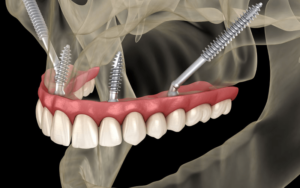

3. Zygomatic Implants in Charlotte, NC

Zygomatic implants are a specialized solution for individuals experiencing severe bone loss in the upper jaw, offering a stable foundation for a permanent upper bridge. Unlike traditional implants, these are considerably longer and are strategically anchored at an angle into the dense zygomatic bone, commonly referred to as the cheekbone.

Zygomatic implants are a highly effective and reliable dental solution offered in Charlotte, particularly for patients requiring upper jaw restorations. At Premier Dental, this advanced procedure is expertly performed by skilled surgeons, delivering numerous key advantages:

- Patients leave with fully functional, fixed teeth on the same day of the procedure.

- Zygomatic implants eliminate the need for upper dentures, providing a more natural and durable alternative.

- By anchoring into the cheekbone, they remove the need for bone grafting, simplifying the process.

- The treatment significantly shortens the timeline for future implants, bridges, or upper jaw restorations.

- Compared to traditional implant options, zygomatic implants are a more cost-effective solution.

- IV sedation ensures a comfortable, stress-free experience throughout the procedure.

- Recovery is fast, allowing most patients to return to daily activities shortly after surgery.

- Extractions and implant placement are usually completed in a single appointment, minimizing inconvenience.